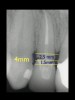

Figure 4  CLINICAL GUIDELINES  The minimum distance needed is 2.5 mm from the osseous crest to the final margin placement to avoid biologic-width impingement. This measurement is meant as a guideline and not an absolute number, as it has been shown to have individual variability. This gives a clinical guideline of 4 mm consisting of 1.5 mm of tooth structure and 2.5 mm biologic width.

Figure 4

Figure 5  CLINICAL GUIDELINES  The minimum distance needed is 2.5 mm from the osseous crest to the final margin placement to avoid biologic-width impingement. This measurement is meant as a guideline and not an absolute number, as it has been shown to have individual variability. This gives a clinical guideline of 4 mm consisting of 1.5 mm of tooth structure and 2.5 mm biologic width.

Figure 5